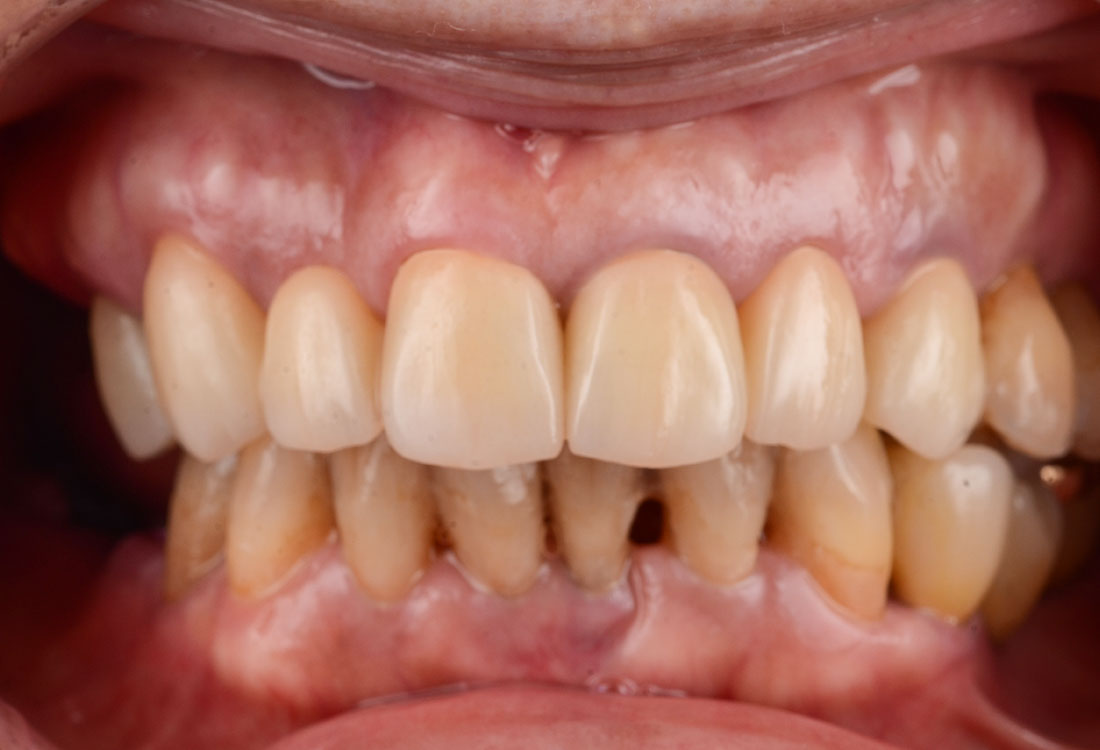

ご相談内容

- 歯の形と見た目が気になる

- 真っ白ではなく色を元の歯の色に合わせてほしい

治療内容

今回は着色したジルコニアを選択しました。

治療後

着色した被せ物を使うことでとても自然な仕上がりになりました。